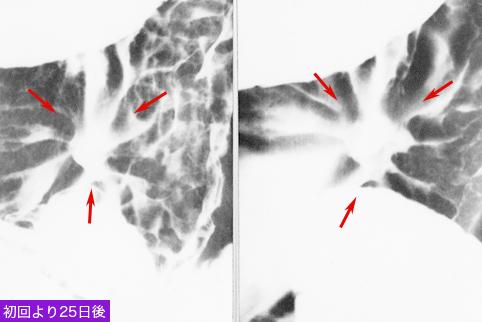

질환(병리주체)의 분류 악성 상피성종양/선암

부위(장기별) 위(부위)/체부

검사방법 X-P

종양의 육안분류 0형(표재형)/III형(III+IIc)

종양의 최대경(밀리미터) 20~24

종양의 심달도 m